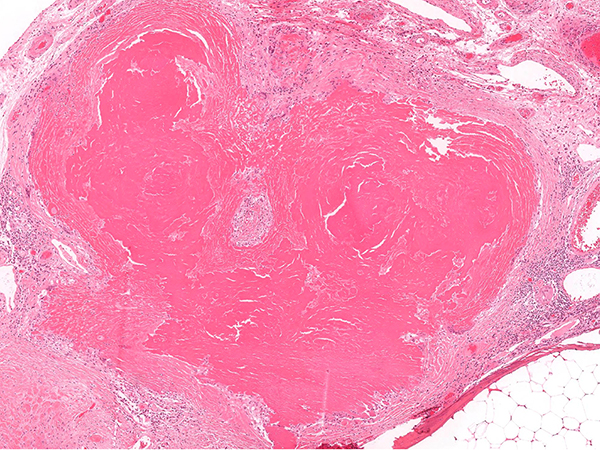

Clinical History: A 70-year-old male with adenocarcinoma in the left upper lobe. Intraoperatively an abnormality was identified on the visceral surface of the left lower lobe that was suspected intraoperatively to represent an ipsilateral metastasis of the lung cancer. An upper lobe lobectomy and wedge of the left lower lobe lesion was performed. The upper lobe demonstrated an acinar predominant adenocarcinoma. A nodular area was identified in the lower lobe and representative hematoxylin and eosin stained photomicrographs of the lesion are shown in figure 1-3. The lesion was negative for Congo Red but demonstrated strong bright crimson red staining on a Masson Trichrome (figure 4). A comparison composite is presented in figure 5 with different histochemical stains. A clonal Kappa expressing population of plasma cells was identified (figure 6). Electron microscopy demonstrated osmiophilic material forming aggregates of granular electron-dense deposits adjacent to entrapped collagen fibers (figure 7). Subsequent bone marrow and further work up did not demonstrate a systemic plasma cell neoplasm. Note: Non-relevant clinical history may have been omitted or altered to protect patient privacy.

The diagnosis of LCDD should be suspected when glassy eosinophilic deposits are identified that are negative for Congo Red staining. Since Amyloid is much more common than LCDD a practical point is to first repeat the Congo Red staining before embarking on a diagnostic (mis)adventure. It is advisable to confirm with your lab that sections stained for Congo Red have been cut as thicker sections (ideally 8-10 microns) as standard thickness sections (< 5 microns) can be falsely negative on Congo Red histochemical stains. As outlined in figure 5 some other commonly available stains (Masson and Movat) demonstrate distinct staining characteristics and can be used to help classify the eosinophilic deposits. Masson trichrome produces a visually striking strong bright crimson red staining (figure 4) in LCDD. While not available in all labs Sulfated Alcian blue can also be used to help distinguish light chain deposits with LCDD staining ‘salmon’ pink and amyloid a ‘seafoam’ green.